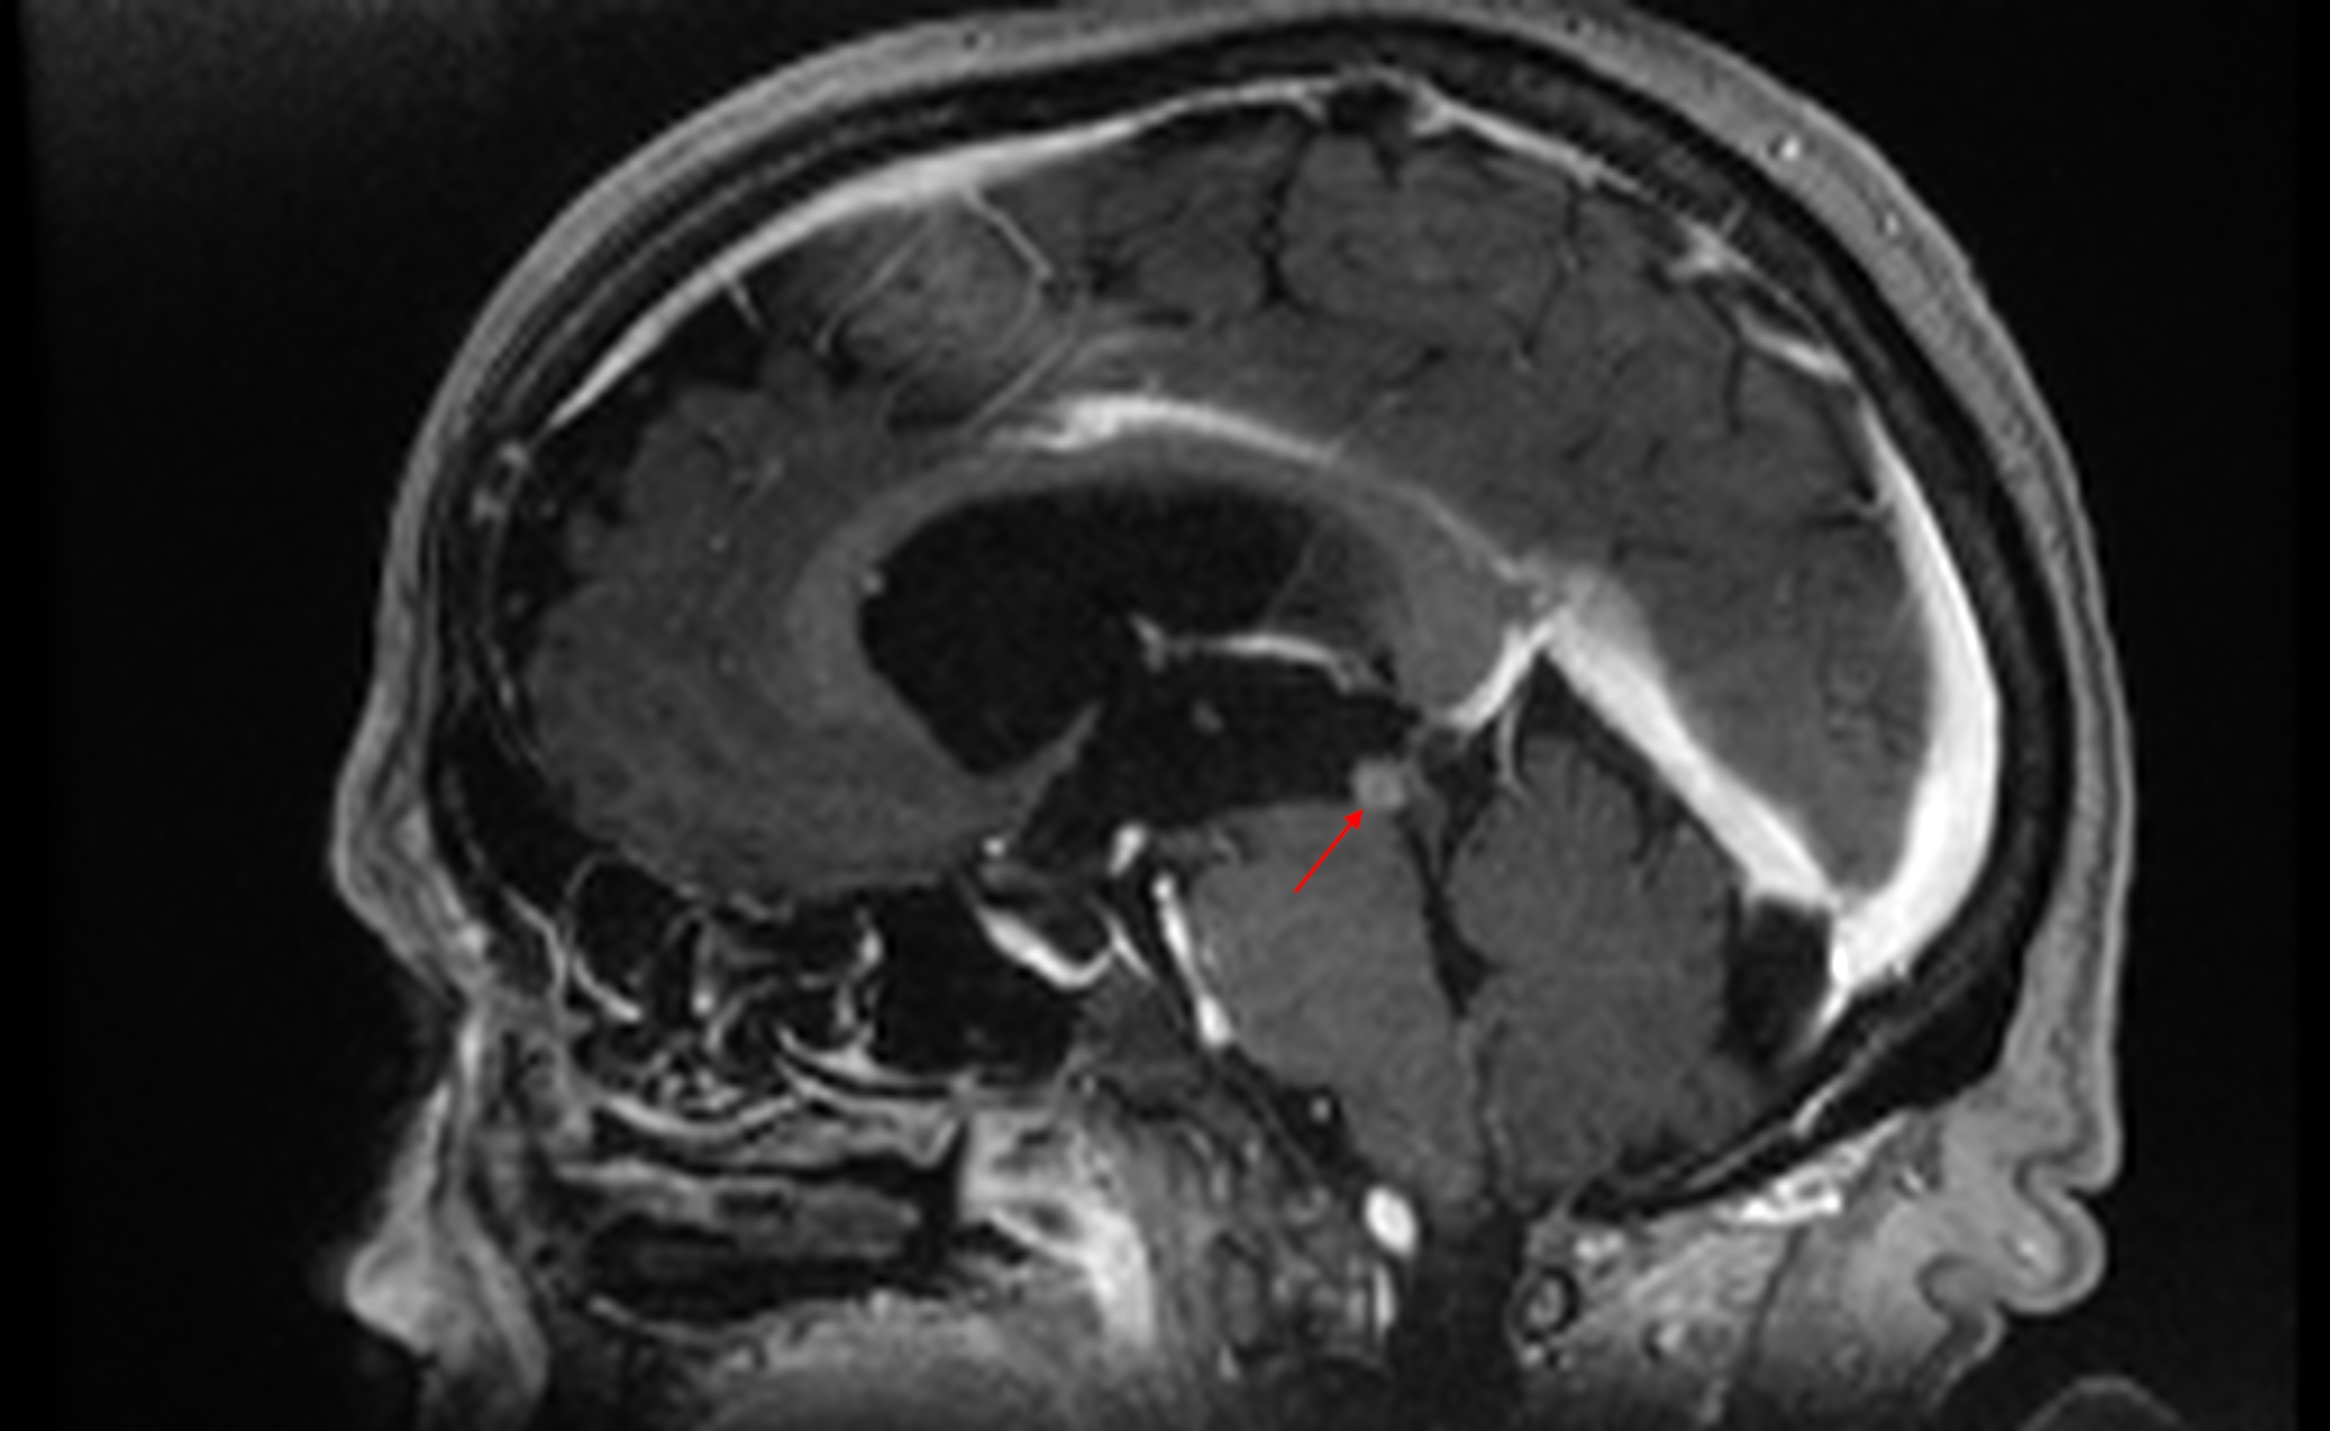

Pathologies of the pineal gland region are frequently encountered in daily neurosurgical practice. It is important to remember that, besides usually asymptomatic pineal gland cysts, neoplasms of a different origin may also occur in this region. The rarity of the most dangerous lesions – pineal gland apoplexy and pineal tumors – might cause problems with proper diagnosis and treatment. Their occurrence is commonly associated with symptomatic hydrocephalus caused by aqueductal stenosis. Currently, in such cases, endoscopic procedures, including endoscopic third ventriculostomy (ETV), are commonly and widely chosen as treatment options. Endoscopic procedures not only enable decompression of hydrocephalus but also further diagnosis of its cause. Herein, we present 3 case reports of endoscopic treatment with ETV performed in patients with hydrocephalus related to pineal region pathologies.